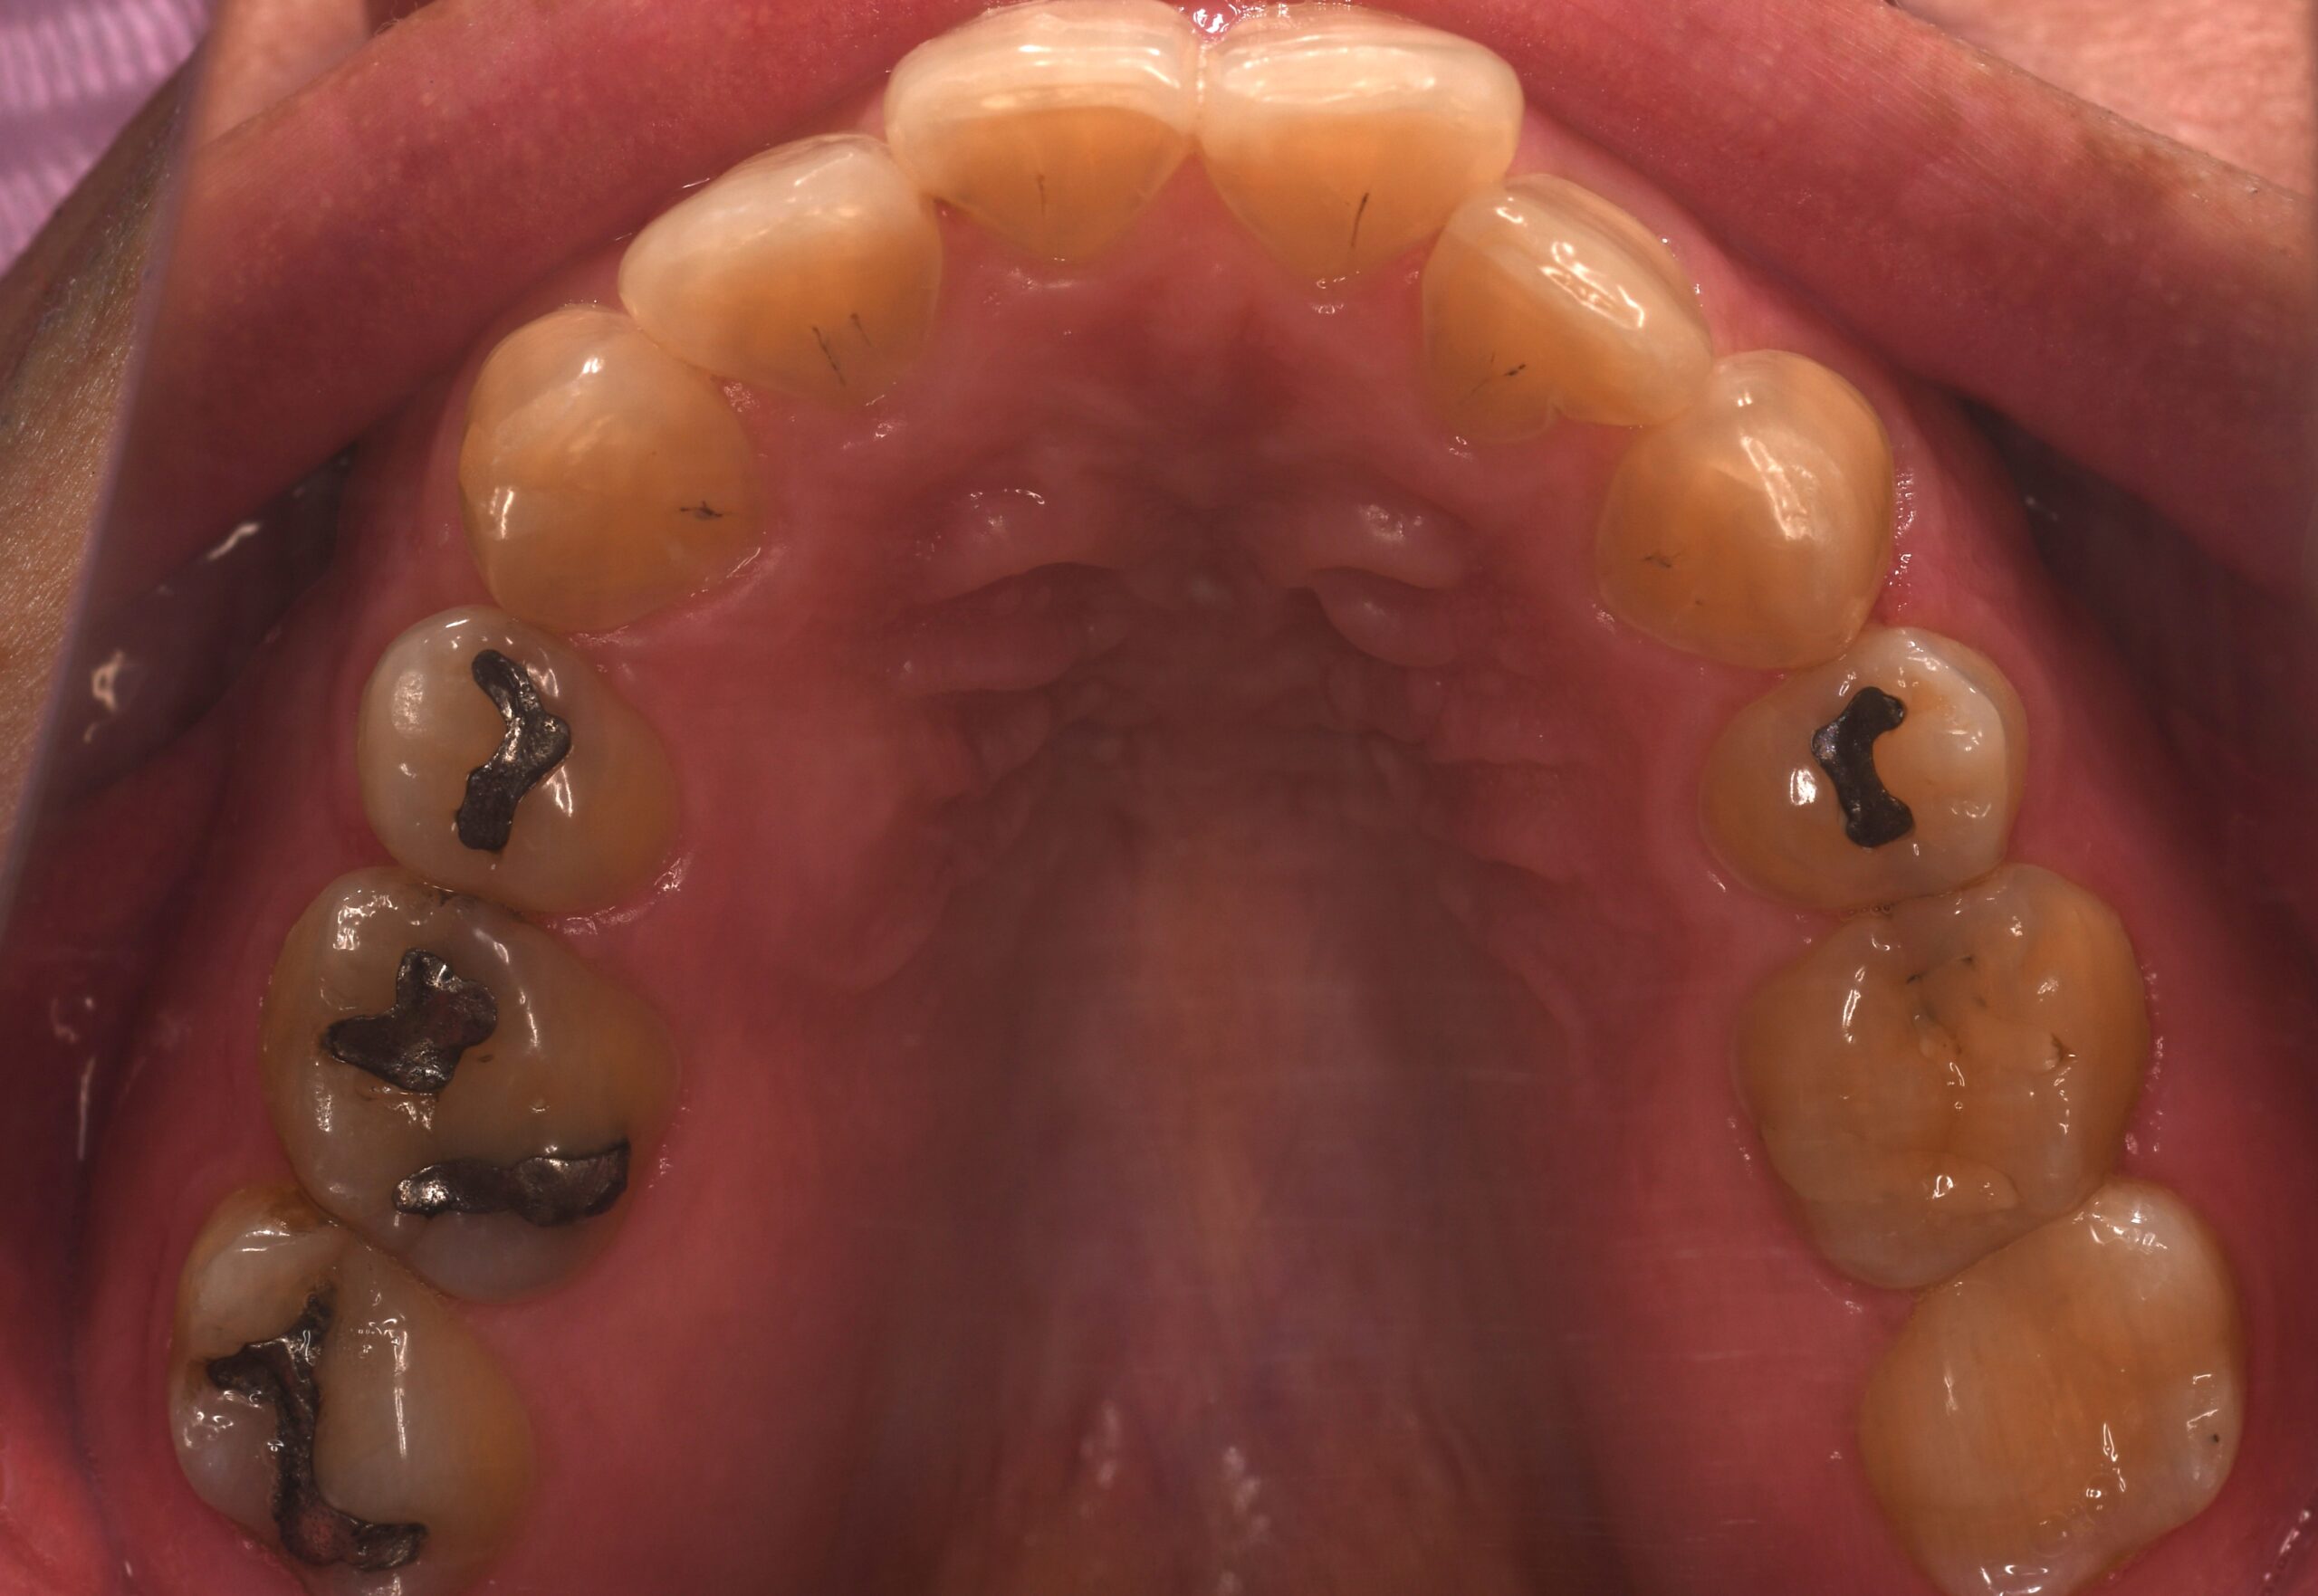

BEFORE

| 年齢 | 45歳 |

|---|---|

| 主訴 | 矯正治療の後戻りを治したい |

| 症状 | 上下両側第一小臼歯抜歯による矯正既往を有する叢生症例 |

| 治療内容 | 上下両側第一小臼歯抜歯による矯正既往を有する叢生症例と診断し非抜歯(上下両側第一小臼歯抜歯済み)でマウスピース型(カスタムメイド)矯正(歯科)装置を用いて治療を行いました。 |

| 抜歯部位 | 非抜歯(上下両側第一小臼歯抜歯済み) |

| 治療期間 | 6か月 |

| 費用(税込) | 990,000円(税込)別途処置料 |

| 治療のリスク | 虫歯、歯周病の悪化、歯肉退縮、歯根吸収、顎関節症の悪化、後戻り |